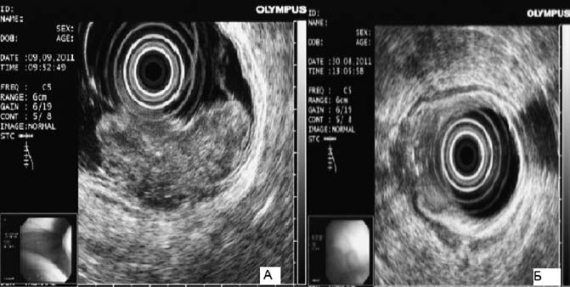

Рис. 63. Эндоскопическая ультрасонография пищевода при раке желудка: А – большая опухоль; В – небольшая опухоль с прорастанием мышечной оболочки

Эндоскопическое ультразвуковое исследование. Эндоскопическая ультрасонография существенно расширяет возможности диагностики рака верхних отделов желудочно-кишечного тракта.

При обследовании больных с опухолями кардиоэзофагеальной зоны эндоскопическое УЗИ позволяет выявить точные границы поражения стенки пищевода и желудка. При этом существенную роль играет решение вопроса о наличии перехода опухоли на пищевод (рис. 63).

Эндоскопическая ультрасонография позволяет выявить даже единичные метастазы в парагастральных лимфатических узлах, в особенности находящихся в зоне поджелудочной железы и в воротах печени.